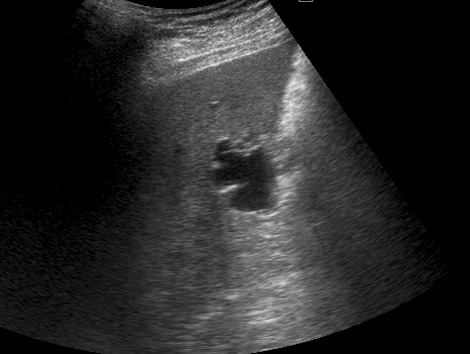

Atlas hígado

2.1. Quistes